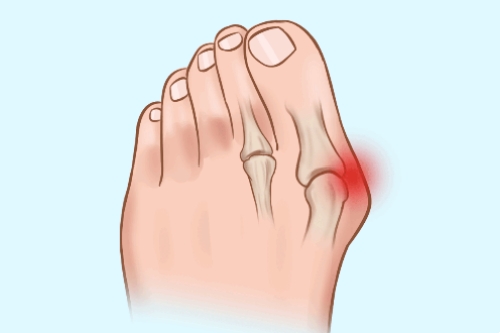

大脚趾外翻是一种常见的足部问题,主要表现为大脚趾向外侧偏斜,超过正常生理角度15度以上。这种情况不仅会影响脚部美观,更重要的是会对日常行走造成困扰。当大脚趾向外翻时,往往会挤压旁边的其他脚趾,导致它们也出现不同程度的变形。同时,大脚趾近端的趾骨头会向内突出,使第一跖骨基部变得明显。在走路时,突出的部位很容易与鞋子发生摩擦,特别是鞋子前部较窄的情况下,这种摩擦会加剧,导致滑液囊发炎,形成厚厚的茧子,让人感到疼痛不适。